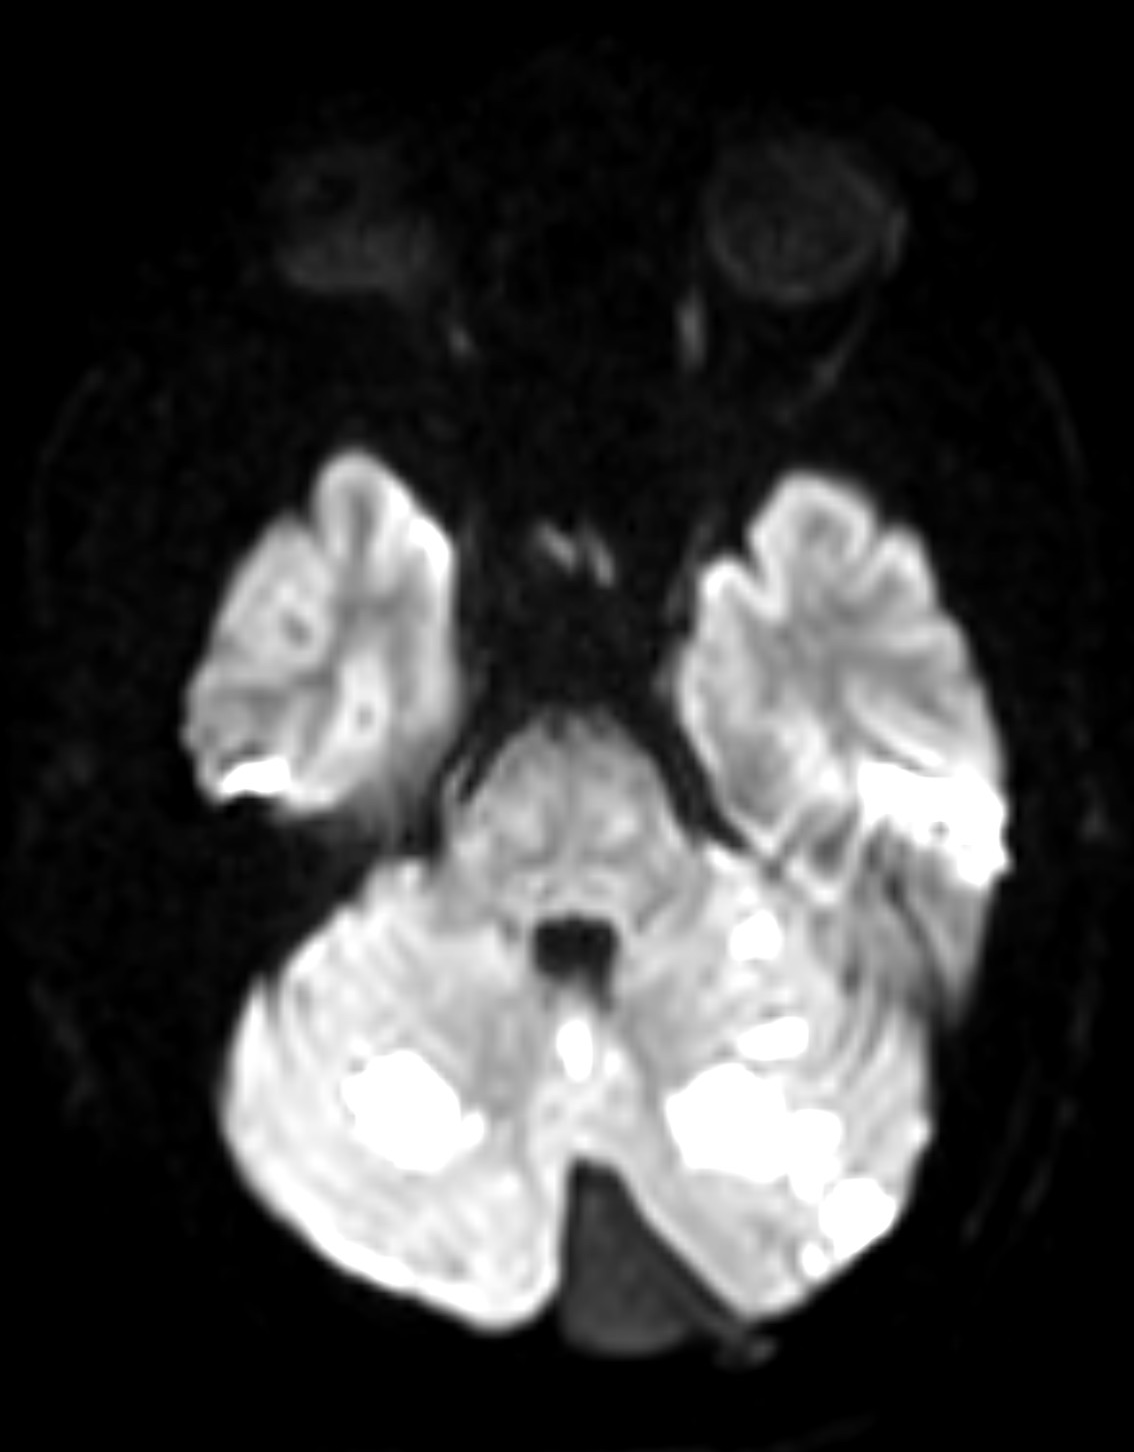

Case Presentation: Vertebral arterial dissections (VAD) while commonly associated with strokes in younger patients (below age of 45) can occur at any age. They are typically seen in patients with head or neck trauma having underlying vascular risk factors including hypertension, hyperlipidemia, tobacco use, and connective tissue disorders. Growing interest in physical fitness has resulted in rigorous workout routines which may pose a risk for strokes and awareness is necessary as signs and symptoms are often vague, leading to delay in diagnosis. We report a rare case of a healthy, 50-year-old male who presented with acute onset imbalance, vertigo, nausea, and non-bloody and non-biliary emesis while working out in the gym. He reported daily weightlifting as a part of his work out but started having nagging left neck pain for the past two days. The patient was given Aspirin prior to arrival to the ED. His NIH stroke scale during ED evaluation was 0, with no disabling deficits. As a result, he was not treated with intravenous thrombolysis. Initial computed tomography (CT) head and CT angiogram (CTA) head and neck were negative for acute intracranial abnormalities. Magnetic resonance imaging (MRI) of the brain demonstrated acute to subacute posterior circulation infarctions of the cerebellum bilaterally, left thalamus, and medial left occipital lobe. Further review of the CTA with three-dimensional post processing confirmed mild irregularity of the left distal extracranial vertebral artery at the level of C1-C2 consistent with symptomatic vertebral artery dissection. Transthoracic echocardiogram did not reveal a patent foramen ovale, valvular pathology, or clots. Neurology evaluated the patient and recommended risk factor modification. The patient was started on aspirin for the dissection. Lipid panel showed LDL cholesterol of 75 md/dL, so he was started on Lipitor 40 mg daily. He remained normotensive prior to and throughout the hospitalization and was discharged home with outpatient follow-up.